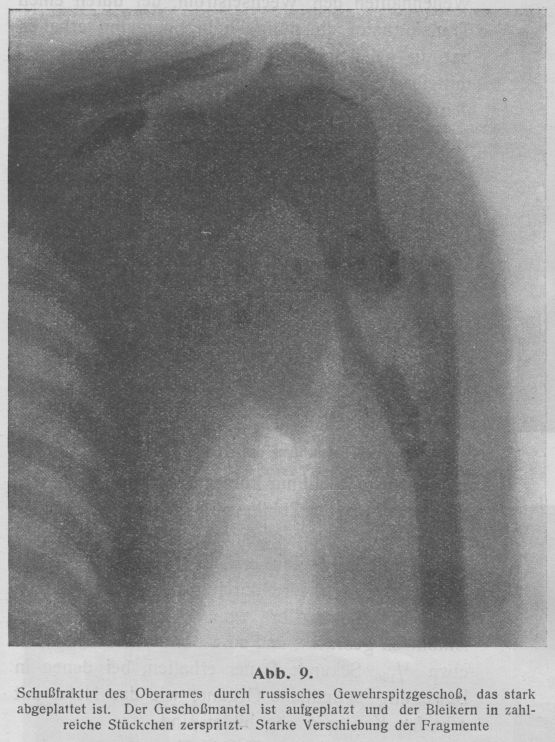

Bei Kriegsverletzungen ist die Röntgendiagnostik unersetzbar geworden. Handelt

es sich doch in den meisten Fällen darum, Sitz und Form von Fremdkörpern – von

Infanteriegeschossen (Abb. 1) und Granatsplittern –

festzustellen, oder Art und Schwere von Knochenbrüchen – Schußfrakturen – zu

untersuchen. Und eine Röntgendurchleuchtung oder -aufnähme gibt über beides

sofort und erschöpfend Auskunft.

Textabbildung Bd. 330, S. 81

Abb. 1. Steckschuß (altes russisches Infanteriegewehrgeschoß) im linken

Darmbein. Einschußöffnung durch Dermatol markiert